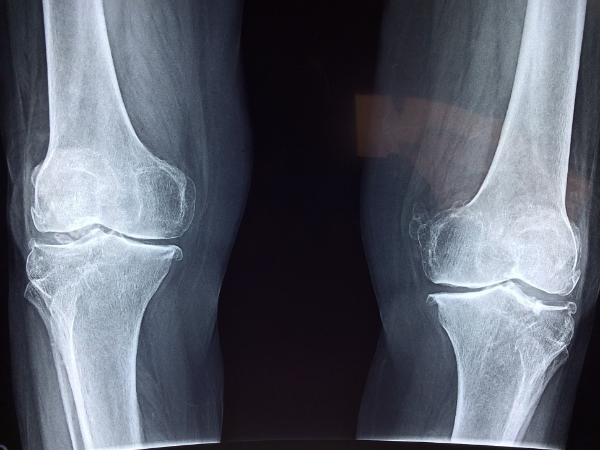

골절 위험 증가

골다공증의 가장 대표적인 초기증상은 골절 위험의 증가입니다. 뼈가 약해지면서 작은 충격이나 낙상으로도 쉽게 골절이 발생할 수 있습니다. 특히 손목, 고관절, 척추, 발목 등의 부위가 자주 골절되므로 주의가 필요합니다. 골절이 발생하면 통증, 부기, 혈종, 움직임 제한 등의 증상이 나타납니다. 골절이 의심되면 즉시 병원에 가서 X-선 검사를 받아야 합니다. 골절이 확진되면 골절 부위에 깁스나 부목을 씌우고, 필요한 경우 수술을 받아야 합니다. 골절이 치료되고 나서도 골다공증 치료를 위해 약물이나 운동 요법을 받아야 합니다.